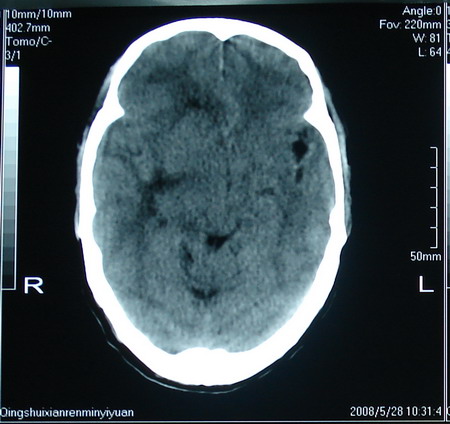

标题: CT13794:M63Y,头颅CT平扫 [打印本页]

标题: CT13794:M63Y,头颅CT平扫

男,63岁,头痛,呕吐,意识模糊一周。无发烧及感染史。

胶质瘤可能性大。

胶质母细胞瘤

胶质母细胞瘤可能,建议增强扫描。

考虑为:胶质瘤可能性大,不排除转移瘤。建议:行进一步检查。

支持右侧丘脑恶性胶质母细胞瘤可能性大,建议增强进一步检查。